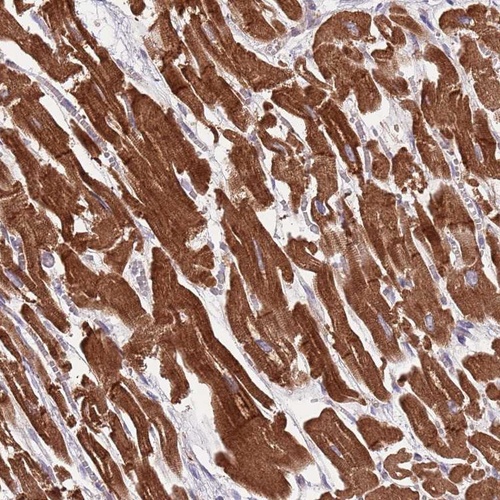

Immunohistochemical staining of human heart muscle shows strong cytoplasmic positivity in myocytes.